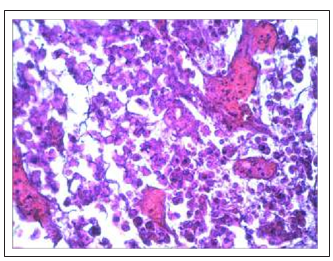

Feroplat® caused more pronounced variety of the spectrum and the degree of manifestation of therapeutic pathomorphosis. Along with the formation of giant cells, the cytomorphological effects in the tumors of animals treated with Feroplat® were characterized by the fact that among the layers of compactly located cells that were almost identical to the cells obtained from control animals, individual patterns were determined, as well as significant sheets of the tumor cells with pronounced signs of hydropic degeneration of the cytoplasm and nuclei. With a large number of these cells, honeycomb look-alike structures were formed (Fig. 11E).

We found thesignificant decrease in the number of mitoses figures. Along with this, extensive fields of necrobiotic cell death, necrosis, theremnantsof dead apoptotic cells were determinedin the various sites of tumors. In some animals, thin-walled blood capillaries were found among dystrophic and non-fibrotically altered tumor cells, filled with blood, and we observed extensive hemorrhages (Fig. 11 F, 11 G). Thedistinctive feature of the tumors after Feroplat® introduction was that in some cells along with dead cells we found the phenomenon of the fibrous organization of the structurally altered tumor tissue which expressiveness had different degree(Fig. 11H, 11I).

Figure 11E: Formation of honeycomb look-alike structures as a consequence of vacuolo-hydroponic dystrophy of DDP-resistant Guerin’scarcinoma cells under the Feroplat®influence (×200).

Figure 11F: Among the dystrophically altered cells of DDP-resistant Guernine carcinoma, there were a lot ofthin-walled blood capillaries filled with blood after the Feroplat® influence (×200)

Figure 11G: Intervention of strains and patterns of tumor cells in the state of nebrobiosis and necrosis with a large number of delated capillaries filled with blood undertheFeroplat® influence (×100).

Fig.11 Changes in the cytoarchitectonics of DDP-resistant Guerin’s carcinoma under the influence of Cisplatin-Ebewe and Feroplat® (coloring with hematoxylin and eosin).